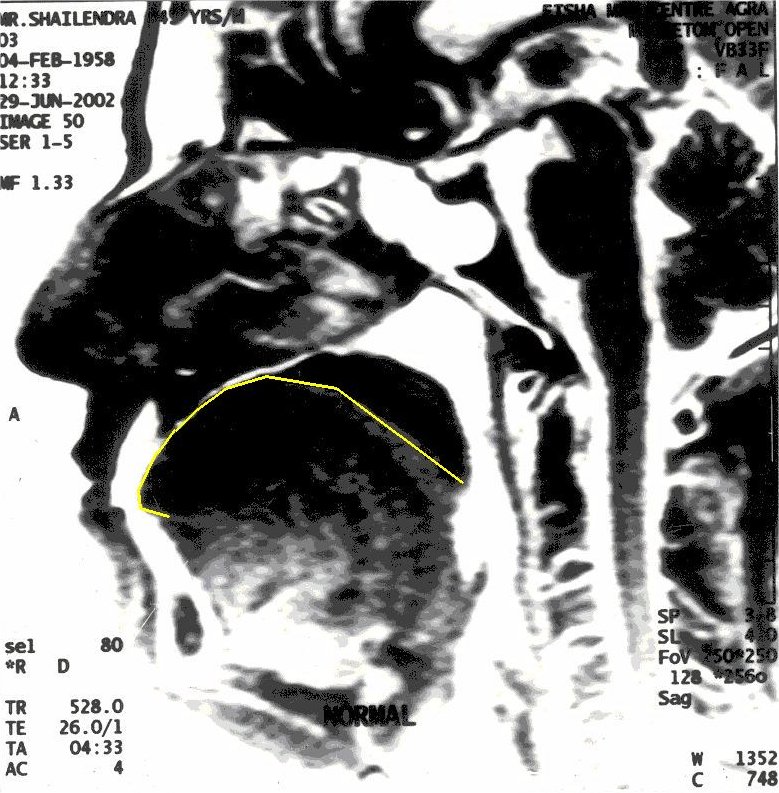

MRI of Yogiraj Shailendra Sharma in Khechari Mudra

Before Khechari Mudra – The position of tongue is outlined in yellow